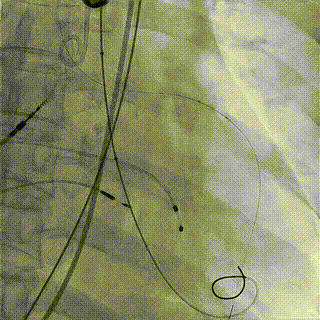

术中影像

1.主动脉根部造影,可见大量反流

2.输送系统过主动脉弓

3.输送系统造影定位

4.释放瓣膜

5.瓣膜完全释放

6.最终造影,反流消失

手术结果

术后食道超声及造影未见瓣周漏,效果良好,手术圆满完成。

瓣膜释放后,食道超声及造影均提示瓣膜无残余反流。